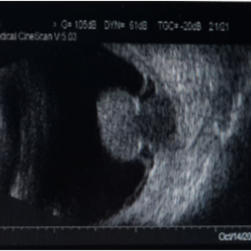

Melanoma-B-Mode Ultrasonography

B-mode ultrasonography of a 52-year-old man with a choriod melanoma.

Photographer: Xing Wang, Ophthalmology Department, Peking University Third Hospital

Condition/keywords: B scan ultrasound